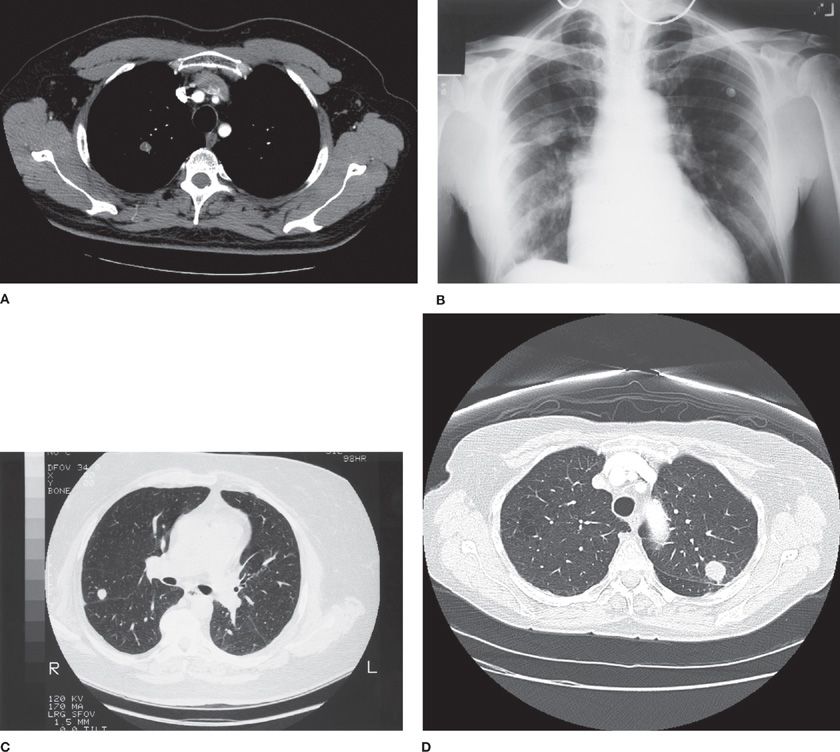

CT (A), UTE (B), HASTE (C), VIBE (D). Left upper lobe spiculated solid Spiculated Nodule Left Upper Lobe A plain film of the chest revealed a 3 cm rounded opacity within the anterior segment of the left upper lobe (lul) located adjacent to the aortic. Malignancy is more common in solid nodules that are 6 mm or greater in diameter. Spns are defined as focal, round, or oval areas of increased opacity in the lung with diameters of. Spiculated Nodule Left Upper Lobe.

CT (A), UTE (B), HASTE (C), VIBE (D). Left upper lobe spiculated solid Spiculated Nodule Left Upper Lobe Spns are defined as focal, round, or oval areas of increased opacity in the lung with diameters of ≤ 3 cm [ 1 ]. Malignancy is more common in solid nodules that are 6 mm or greater in diameter. The characterization of spns is a major concern not only to. You may have one nodule on the lung or several. Spiculated Nodule Left Upper Lobe.